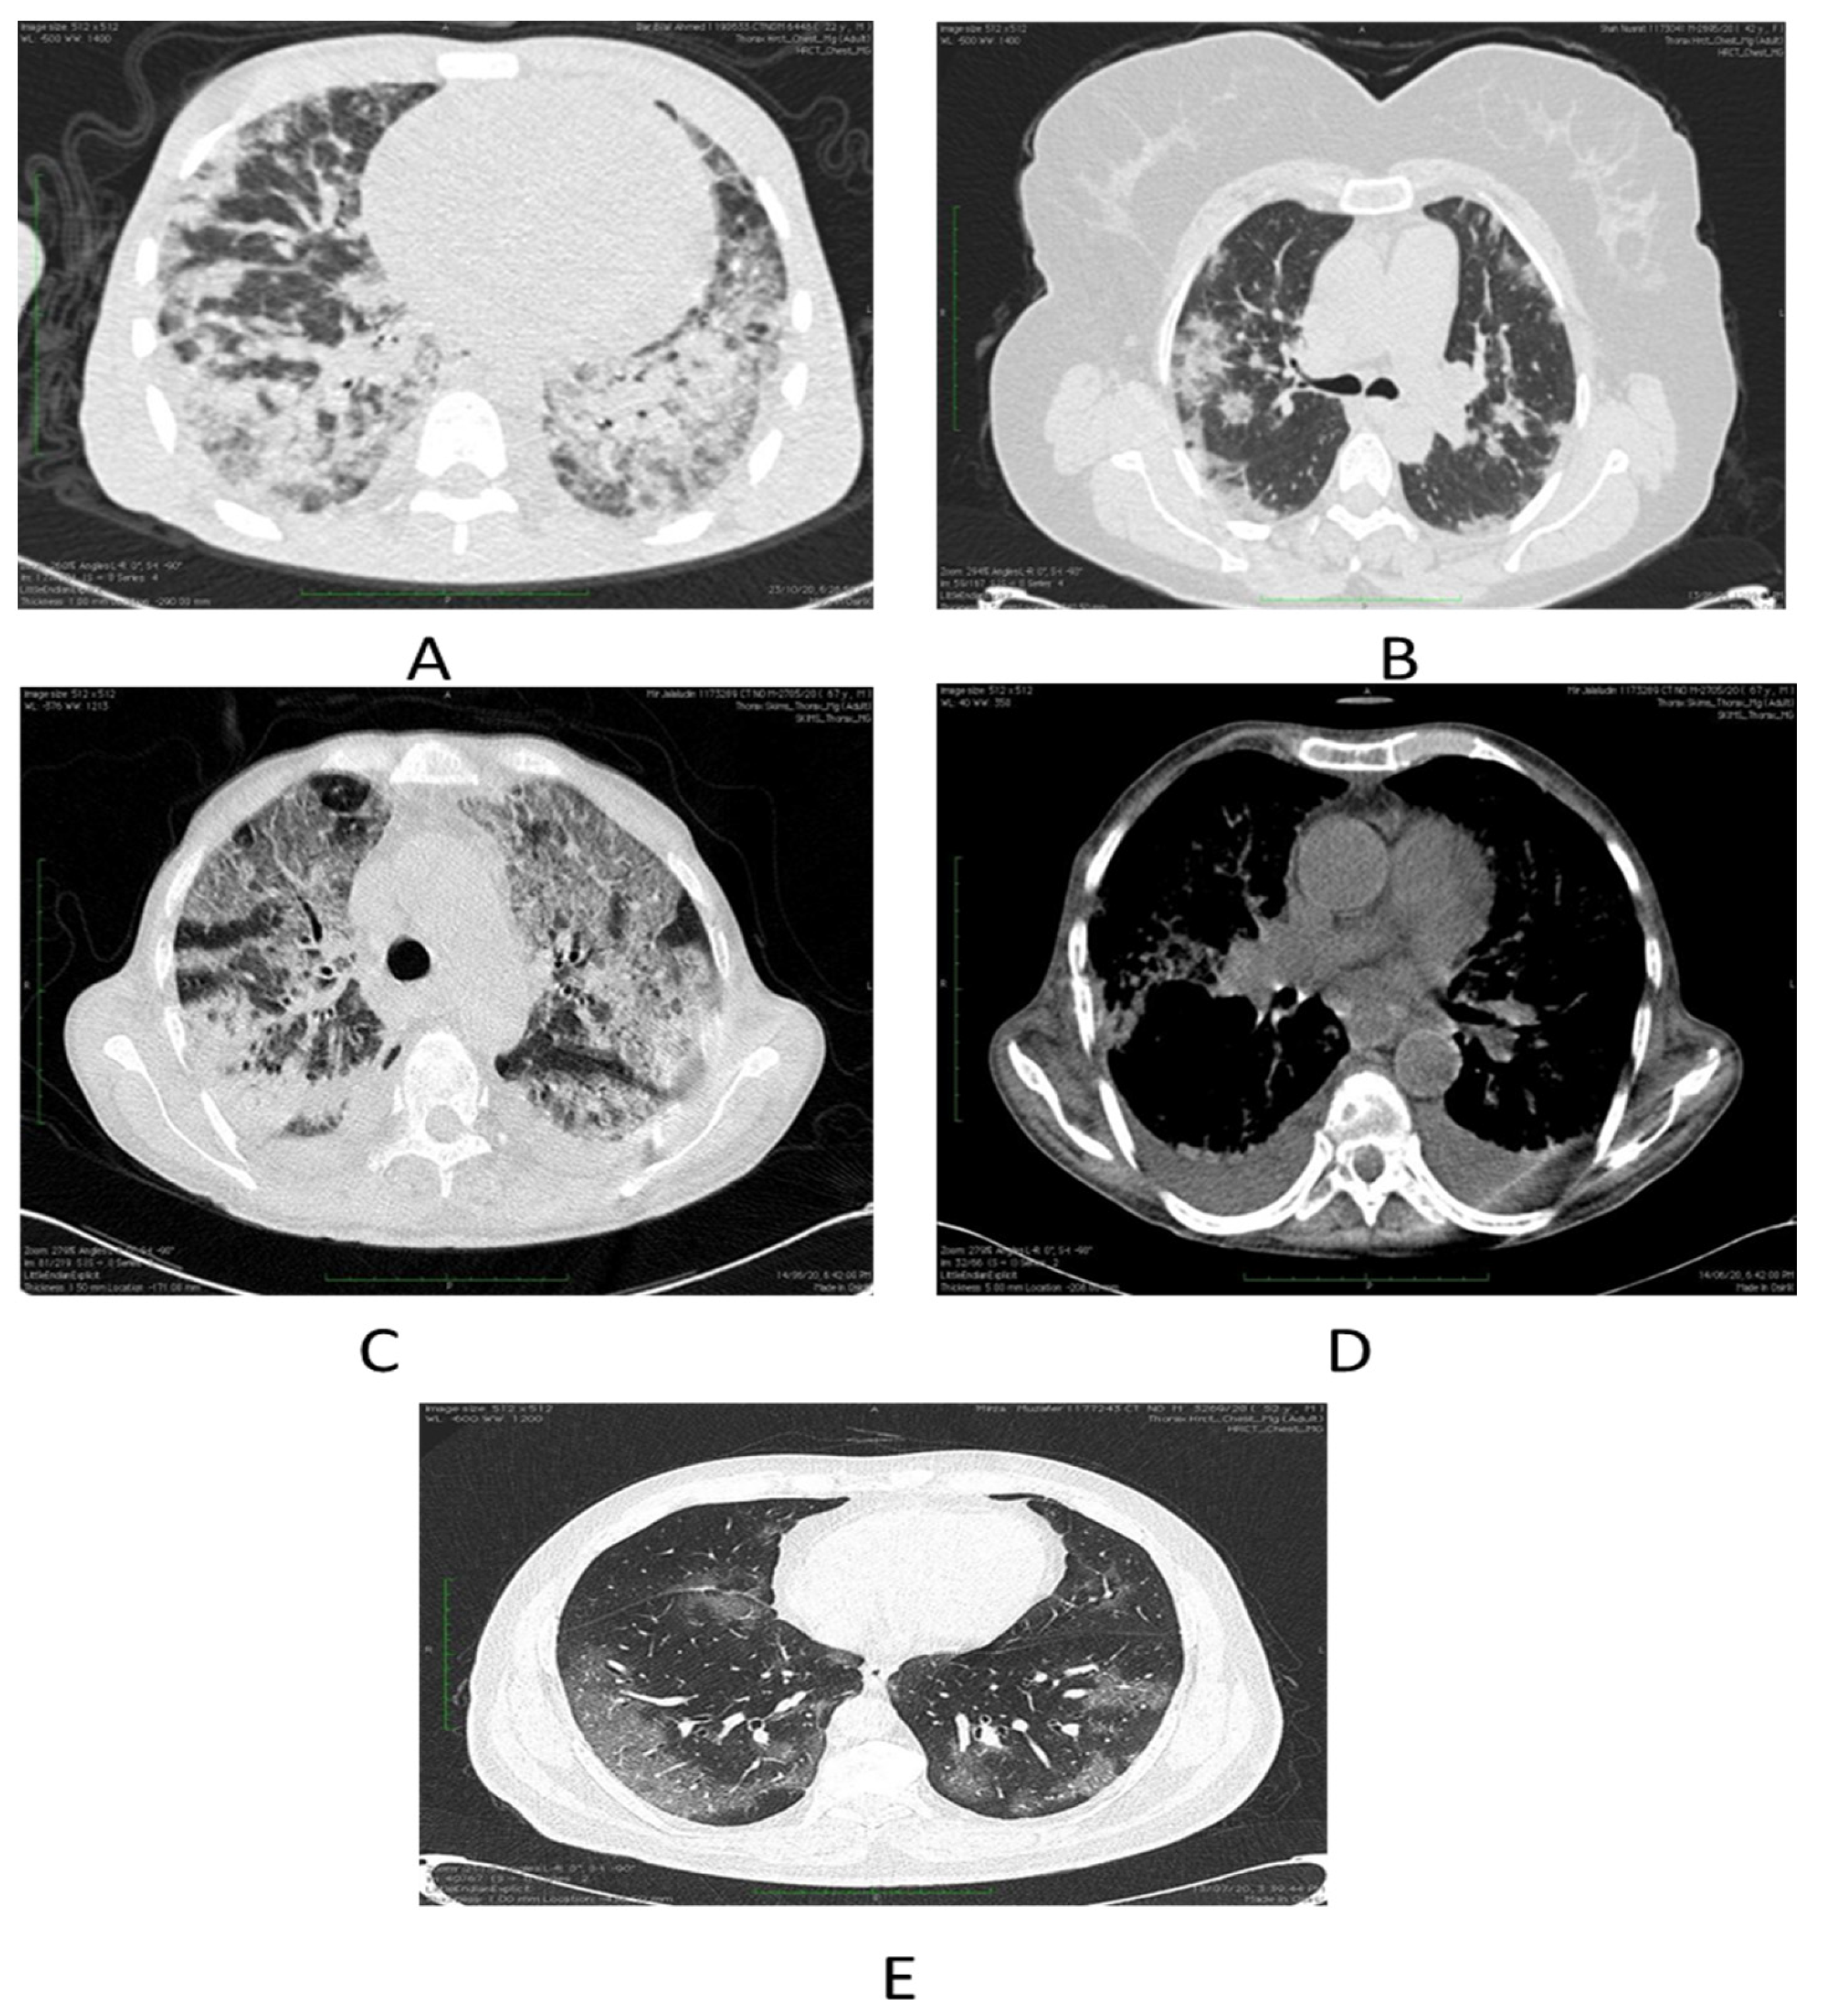

Chest HRCT scans were assessed for the existence and dissemination of ground-glass opacities (GGO’s) which are taken as areas of haziness inadequate to obscure the underlying vascular markings, septal thickening (intra or interlobular), crazy paving, consolidations and other atypical findings favoring COVID-19. The presence of many lobar or patchy ground glass opacities, with or without thickening of the interlobular septae (crazy paving), consolidations, and preponderance of the subpleural and bibasilar tissues, is highly symptomatic of COVID-19 disease (Figure 1).

Figure 1.

(A) Depicts severe COVID-19 pneumonia in a patient in form of consolidations. (B) Shows few patches of nodular consolidations in a patient with moderate disease. (C) Demonstrates combined ground glass opacities and consolidations in a patient with severe COVID-19 illness. (D) Axial chest image bespeaks bilateral effusions. (E) Ground glass opacities indicated by axial chest cuts.

Three patterns of lung involvement are seen (i) Patchy or diffuse GGO’s; (ii) Inhomogeneously distributed collapse and peribronchial opacities; (iii) ARDS -like pattern. Chest radiographs, if available were also assessed and data was collected.